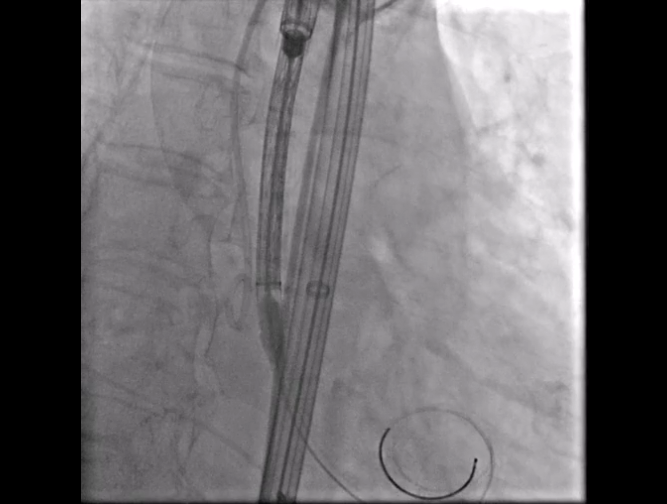

Step 4.输送系统进入:过弓性能优异,悬空通过,整体过程未将鞘管顶起至弓顶部

17.gif